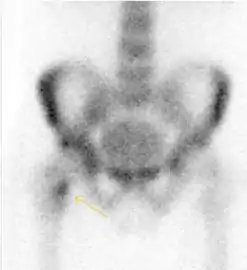

MRI has been shown to have 100% sensitivity and specificity in prospective studies of occult hip fractures. These fractures were diagnosed by bone marrow edema and a low signal fracture line, mainly on T1 or T2 weighted images (Figure 10).[1]

Figure 10:

Stress femoral neck fracture in a young athlete barely visible in X-ray film as a sclerotic line (arrow)[1]

In this case, Tc 99 scintigraphy shows a band of uptake[1]

Furthermore, T1 (left) and DP fat saturated (right) weighted MR images showed the fracture line and a pattern of edema.[1]

Nuclear Medicine

Bone scanning in people with hip pain can be complementary to other imaging studies, mainly in indeterminate bone lesions to clarify whether it is an active lesion with abnormal radiotracer accumulation. Nevertheless, MRI has replaced scintigraphy in the diagnosis of most of these conditions. An example is stress or insufficiency fractures: increased uptake is usually present in around 80% of fractures within 24 h, and 95% of fractures reveal activity by 72 h following trauma, showing an overall sensitivity of 93% and specificity of 95%. MRI is superior to bone scans in terms of sensitivity (99%-100%) and specificity (100%). Moreover, a bone scan does not provide detailed anatomical location of the fracture, and further imaging is usually required.[1]